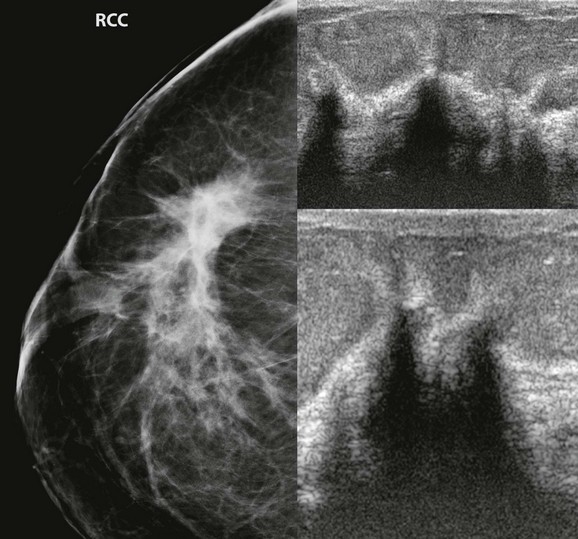

FIGURE 11-5 Tubular Carcinoma.

There is a small spiculated mass in the right breast at 1 o’clock, middle third (arrows). Notice the long spicules along the lateral margin of the mass.